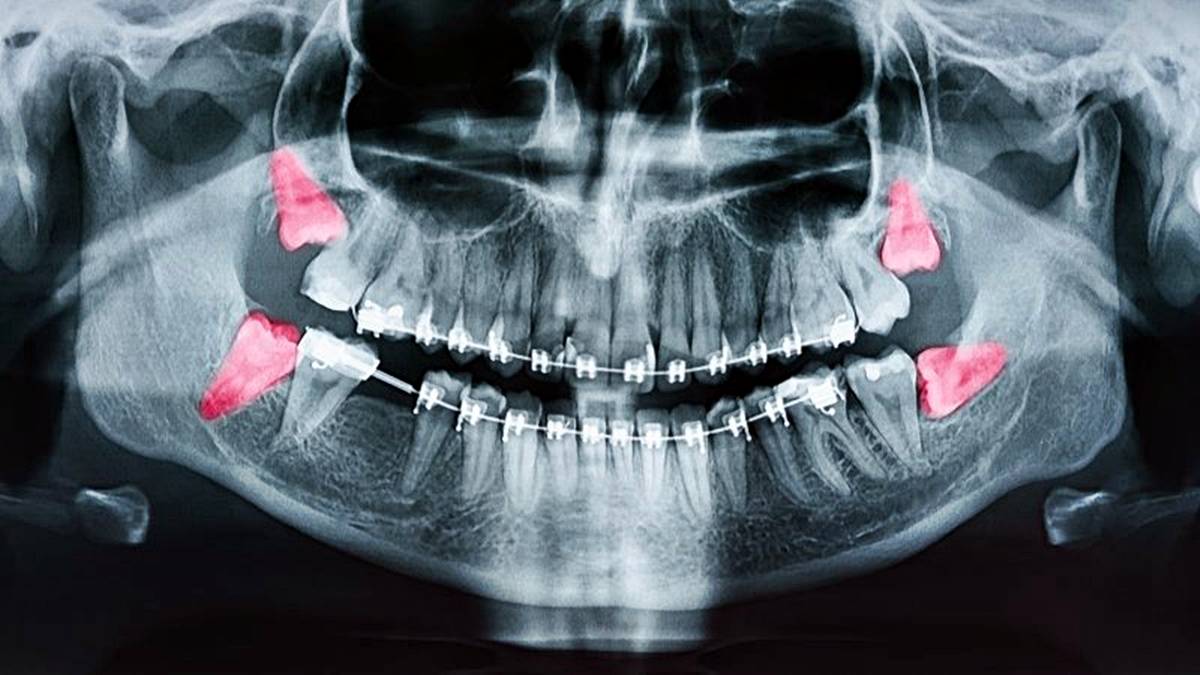

Yirmilik dişlerin güncel olarak yarattığı başlıca sorunlar arasında ağrı, enfeksiyon (perikoronitis), diş eti iltihabı, kist oluşumu ve komşu dişlere baskı yaparak çapraşıklığa yol açması yer alır.

Özellikle tam çıkamayan veya yanlış pozisyonda sürmeye çalışan gömülü dişler, çevrelerindeki kemik ve yumuşak dokuya zarar verebilir.

Bu dişlerin en arkada yer alması nedeniyle temizliklerinin zor olması da çürümeye yatkınlıklarını artırır.

Modern diş hekimliği, bu tür sorunlara yol açan yirmilik dişlerin cerrahi operasyonla çekimini önerebiliyor.